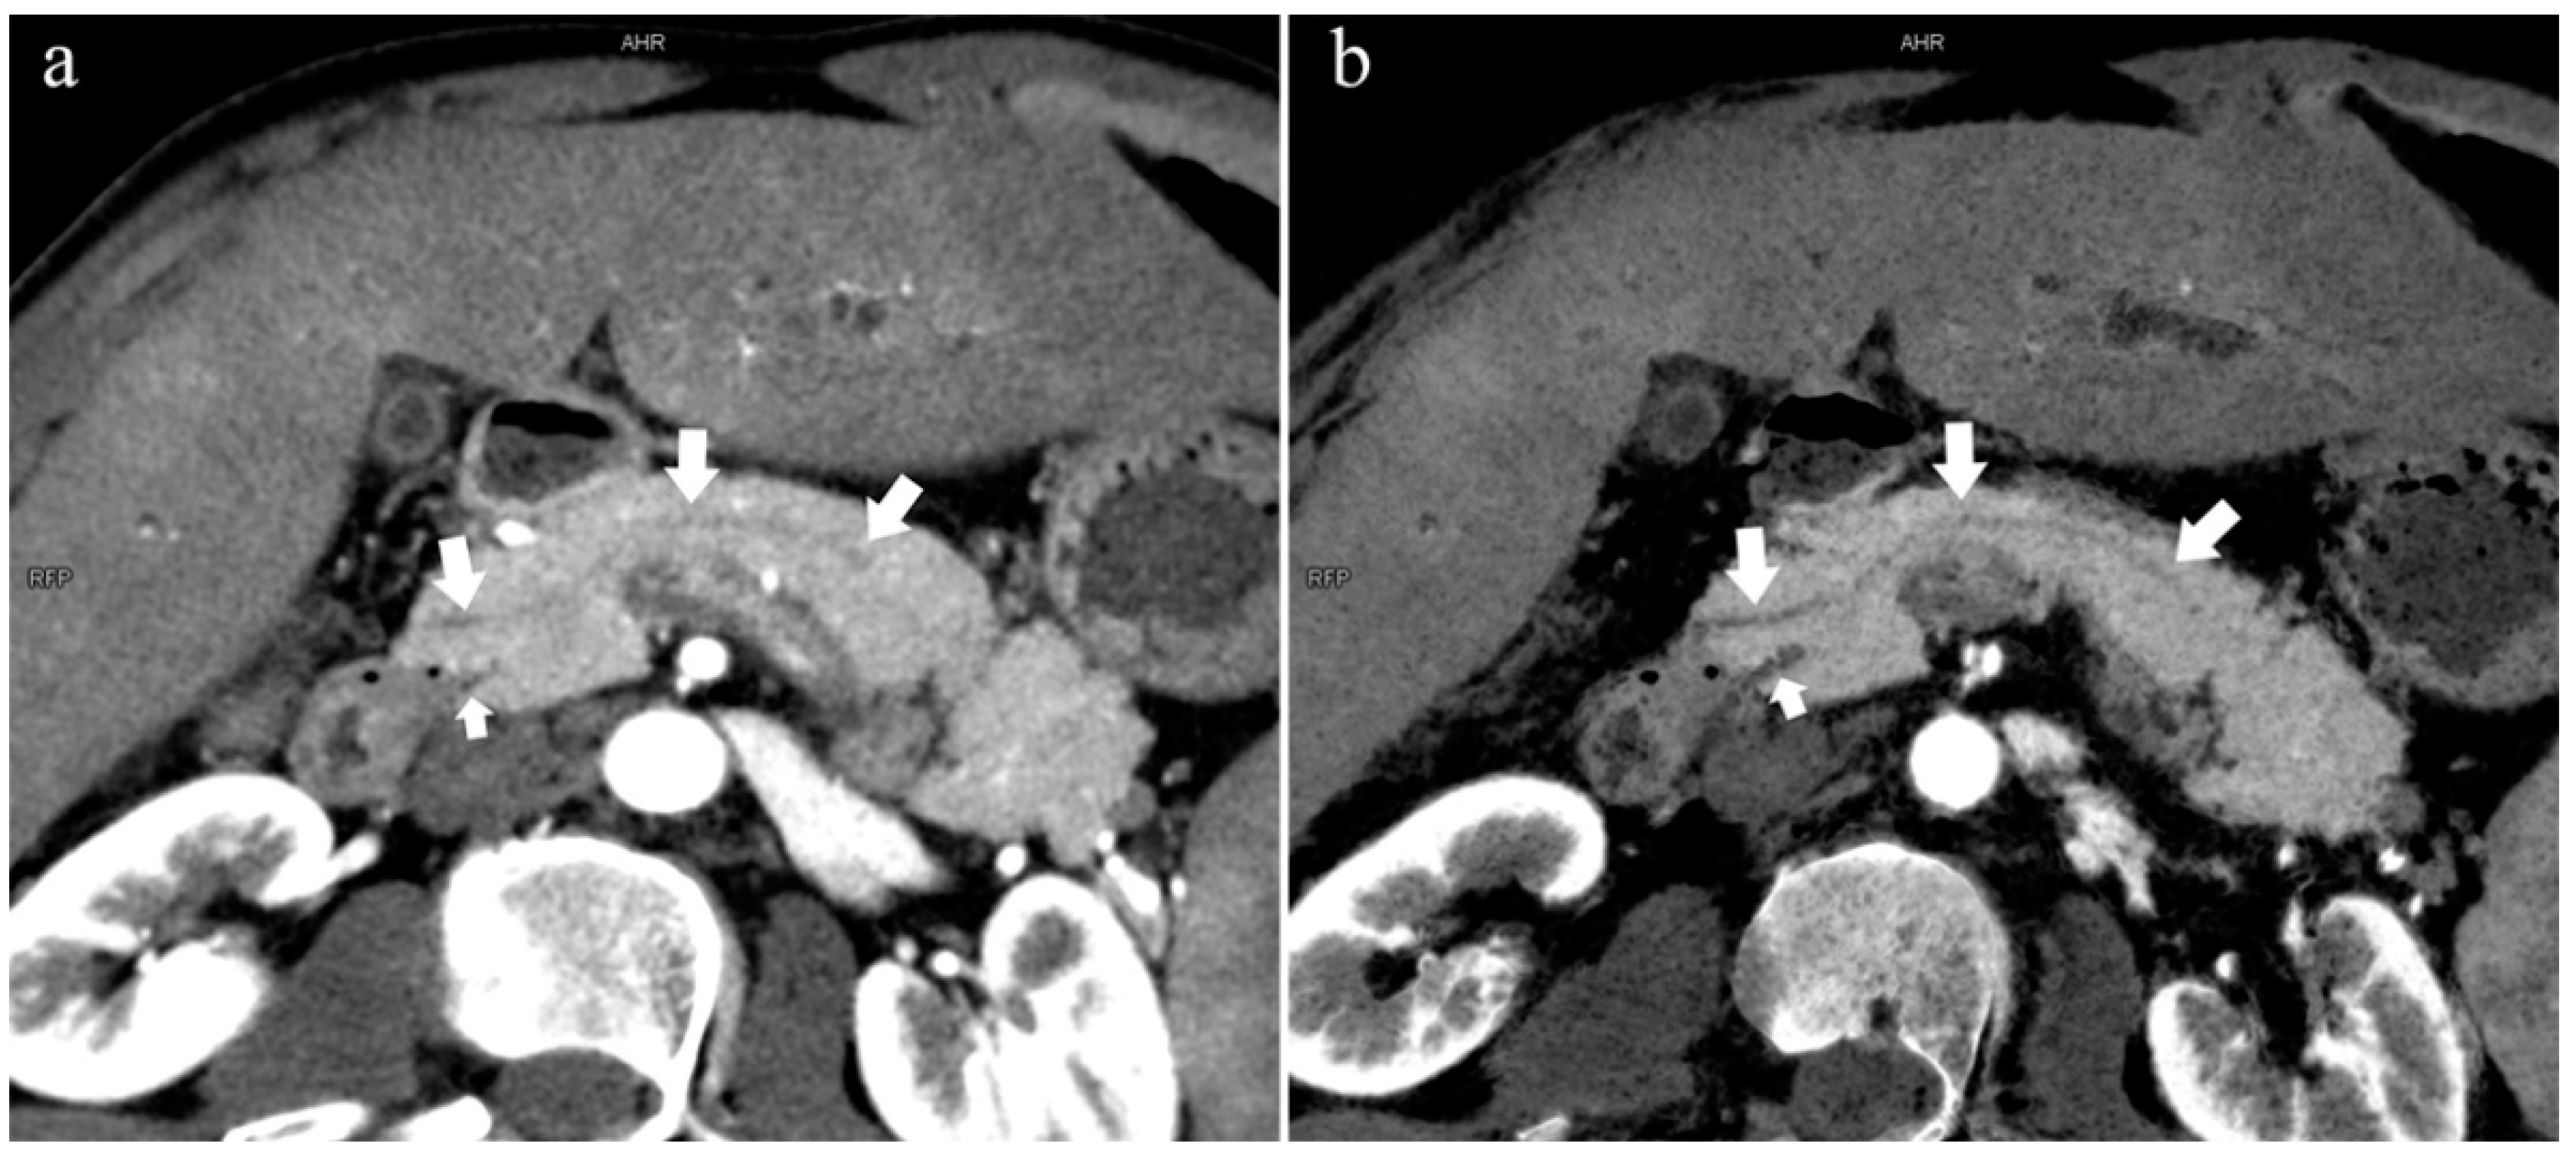

The MPD flowed into the MP, and no APD was the most common anatomical type (type 3b, Figure 4) (58.5%, 473/808); the second type was a classical double division with the double duct structure (type 1, Figure 5) (28.0%, 226/808).

Figure 4.

Type 3b, 63-year-old male patient with AP. (a): MIP [45 keV MEI (+)] shows an S-shaped dilated MPD (long arrow) in the head of the pancreas. APD is not displayed. The fat space around the head of the pancreas is blurred (short arrow). (b): MinIP [45 keV MEI (+)] clearly shows the overall shape of “S”-shaped MPD.